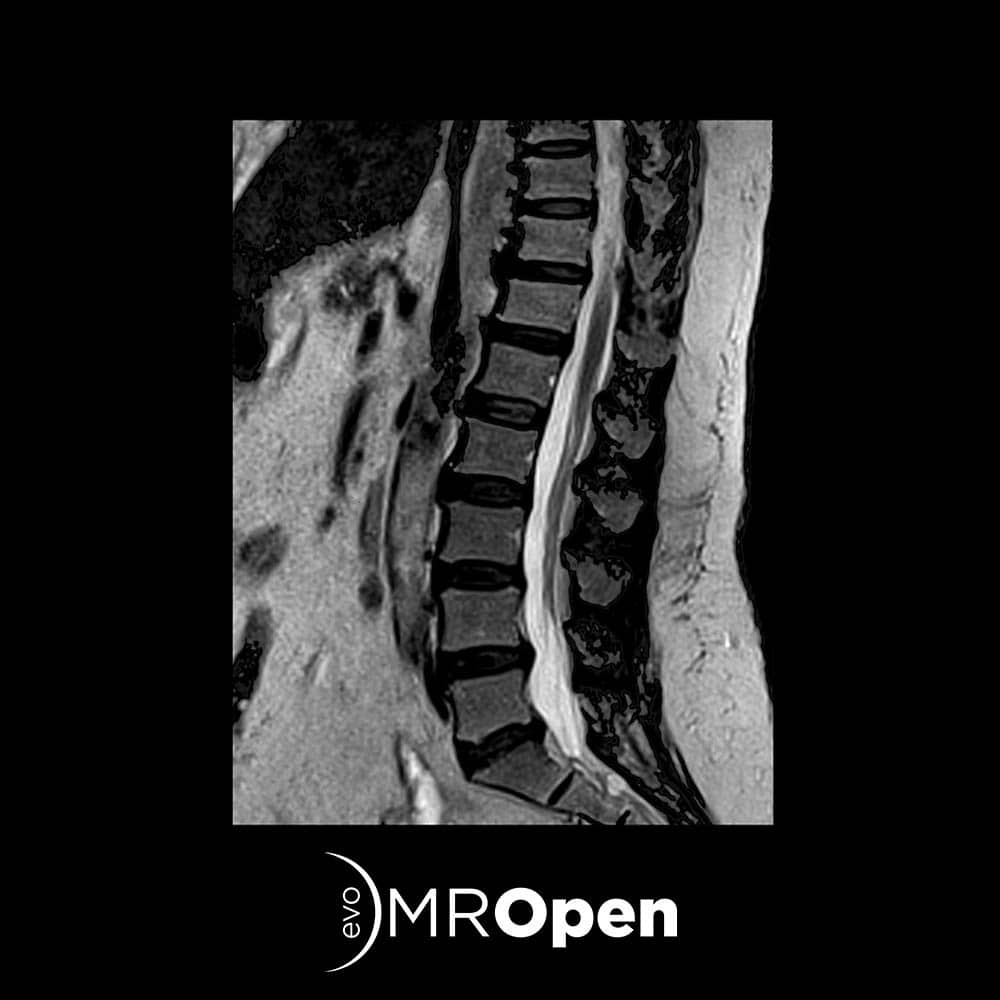

Whole Spine RF Coil

The 8 channels RF coil ensures a perfect signal coverage for whole spine examinations. The operator can perform the entire spine examinations without changing the coil from one anatomical area to the next, reducing the positioning time between between the Cervical, Thoracic and Lumbar spine areas allowing the Whole Spine RF coil to increase the workflow for spine examinations up to 30%.